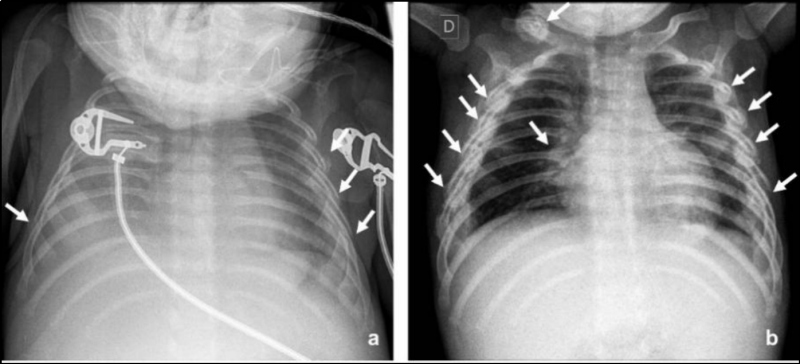

Se consideran fracturas altamente específicas de maltrato físico las costales posteriores y la lesión metafisaria clásica (fractura en esquina y en asa de balde) (Fig. 3)(10,14). Las fracturas costales en lactantes y niños pequeños se han relacionado con maltrato hasta en el 82% de los casos(11). En niños menores de 3 años, el valor predictivo positivo de las fracturas costales como indicador de maltrato es de un 95%(12).

En lactantes fallecidos por maltrato físico, las fracturas más comunes son las costales(13), que en ocasiones no son evidentes en la radiografía por no haber aún desarrollado reacción perióstica y callo óseo (Fig. 4) (13,14,15).

El centellograma óseo también puede realizarse como una alternativa a la seriada esquelética en niños entre 2 y 5 años, ya que la probabilidad de lesión metafisaria clásica es baja en este grupo de edad (Fig. 5). Conway et al. y otros, en un informe de dos estudios y una revisión de la literatura, concluyen que la gammagrafía esquelética es el mejor estudio complementario para la evaluación de la sospecha de abuso infantil(13). La gammagrafía puede identificar fracturas agudas de costillas que no son evidentes en las radiografías, pero es menos sensible en la detección de las fracturas metafisarias (Fig. 6) y fracturas de cráneo (13,16).